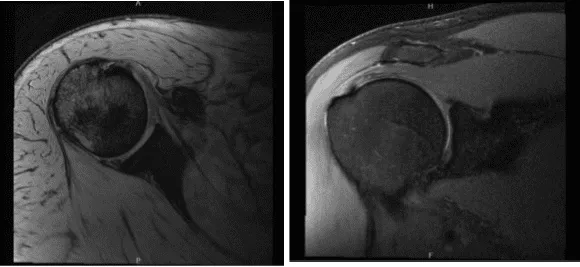

MRI-3T Hombro derecho sin contraste

El médico revisó y discutió la resonancia magnética, y hay una leve supraespinosa y tendinosis infraespinosa. La tendinosis subescapular leve está presente con una ruptura focal de grosor parcial de las fibras medias.

Un pequeño foco lobulado e hiperintenso a lo largo del margen superficial del tendón subescapular probablemente refleja un ganglio pequeño. El tendón menor del árbol está intacto. No se identifica ningún desgarro del manguito rotador de grosor completo. No hay atrofia desproporcionada del manguito rotador.

Existe una leve artrosis acromioclavicular. Está presente bursitis subacromial-subdeltoides leve. Se mostró que presenta desgarro parcial del manguito rotador, así como desgarro del tendón del bíceps, además de espolón subacromial y artritis AC. El tendón del bíceps se encuentra dentro del surco bicipital.

Existe una tendinosis leve del bíceps, preferentemente en su porción intraarticular, con una ruptura lineal de grosor parcial de la porción intraarticular del tendón del bíceps que se extiende distalmente hasta el nivel de la ranura bicipital proximal. Tiene tenosinovitis mínima en el bíceps

Hay una rotura del labrum superior que se extiende hacia el labrum anterior superior y posterosuperior. No se identifica ningún defecto condral focal sobre la articulación glenohumeral. Hay líquido residual presente dentro de la articulación glenohumeral. No hay fractura aguda ni osteonecrosis.

Tendinosis leve del manguito rotador multifocal con una ruptura focal de grosor parcial del tendón subescapular. No hay desgarros del manguito rotador de grosor total. Desgarro lineal de grosor parcial de la porción intraarticular del tendón del bíceps que se extiende distalmente hasta el nivel del surco bicipital proximal, superpuesto a tendinosis leve, con tenosinovitis mínima en el bíceps.

Desgarro del labrum superior que se extiende hacia el labrum anterior superior y posterosuperior. Artrosis leve de la articulación acromioclavicular. Bursitis subacromial-subdeltoides leve.